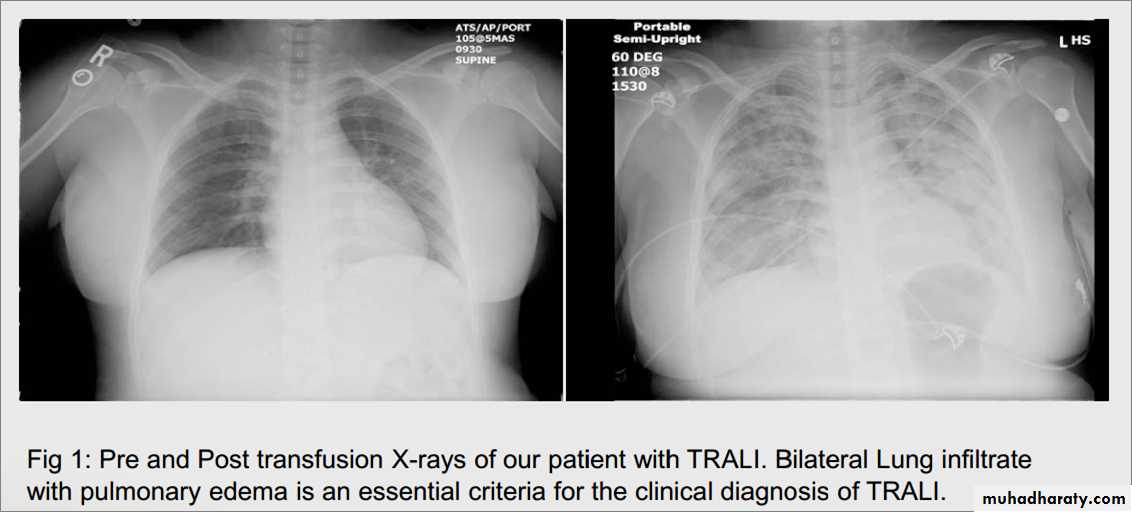

(CVP IS NORMAL )Transfusion-related acute lung injury (TRALI) is the leading cause of transfusion-related mortality. It is characterized by the development of acute lung injury within 6 hours of transfusion of erythrocytes, platelets, or FFP. TRALI is mediated by initial priming of neutrophils in the recipient's lung parenchyma (endothelial damage, for example) followed by their activation by anti-HLA and antineutrophil antibodies present in donor plasma. Signs and symptoms escalate quickly and include dyspnea,COUGH , hypoxia, fever, chills, and hypotension. Chest radiograph reveals diffuse bilateral pulmonary infiltratrate.

CXR ( TRALI)